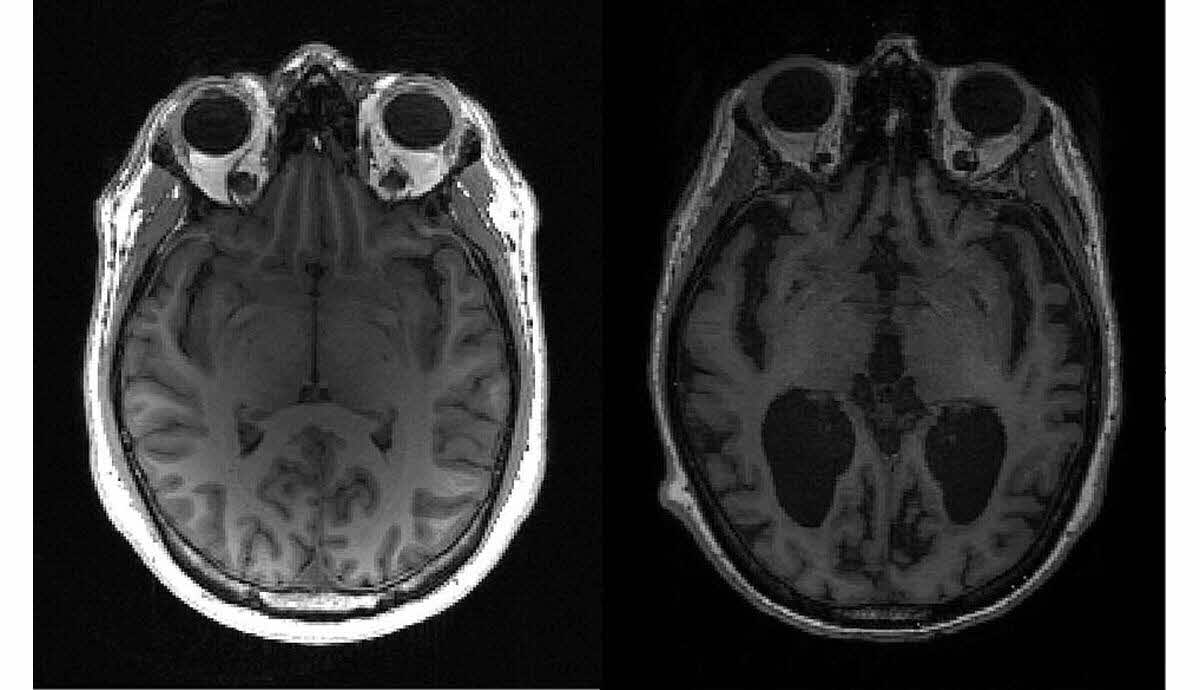

La relation entre la maladie d’Alzheimer et le cancer semble, a priori, être fondamentalement antagoniste. D’un côté, Alzheimer est une maladie neurodégénérative qui vole lentement les souvenirs et les capacités cognitives des personnes touchées. De l’autre, le cancer se manifeste comme une prolifération incontrôlée des cellules, attaquant le corps de manière souvent insidieuse. Pourtant, les chercheurs ont observé un phénomène étonnant : les personnes atteintes de la maladie d’Alzheimer semblent développer moins fréquemment des cancers que celles qui n’en souffrent pas.

Une étude menée par le MUSC Hollings Cancer Center a révélé que les adultes de plus de 59 ans atteints d’Alzheimer ont un risque de développer un cancer jusqu’à 21 fois inférieur à celui de la population générale. Ce chiffre formidable incite à s’interroger sur les mécanismes biologiques sous-jacents. Une question essentielle germe alors : comment une protéine réputée nocive pourrait-elle offrir un tel avantage?

La β-amyloïde, principale responsable des enchevêtrements neurofibrillaires dans le cerveau des malades d’Alzheimer, est réputée pour ses effets dévastateurs sur les neurones. En perturbant les circuits synaptiques, elle engendre des troubles sévères de la mémoire et des fonctions cognitives. Cependant, dans un contexte différent, la β-amyloïde semble revêtir une facette inattendue qui mérite d’être explorée.